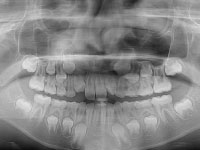

インビザライン治療に必要な検査(レントゲン・セファロ・CT・iPod撮影・iTero)を行います。

- レントゲン撮影

- お口のレントゲン写真を撮影

-

- セファロ撮影

- 矯正専用のレントゲン写真を撮影